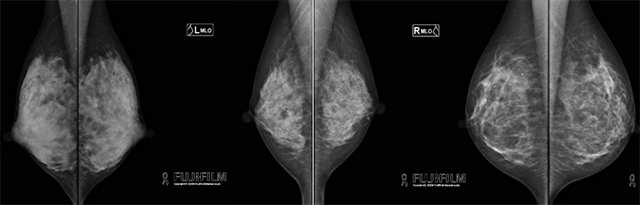

当院では世界最小(小さければ小さいほど病変を見つけやすくなる)の画質50μmを持つ富士フィルムメディカル社“アミュレット”という直接変換方式フラットパネル装置を導入しました。

最新の画像処理技術を用いることにより病変部(石灰化、腫瘤)をより精細に描出し、更に被ばく線量を最小限にすることができ、検査時間も短縮することが可能となり、受診者のみなさまの負担を軽減することができるようになりました。

角度を変えて2方向撮影しますので、右乳房、左乳房で合計4枚撮影します。(必要に応じて枚数が変わる場合もあります。)検査時間は、約10~15分です。